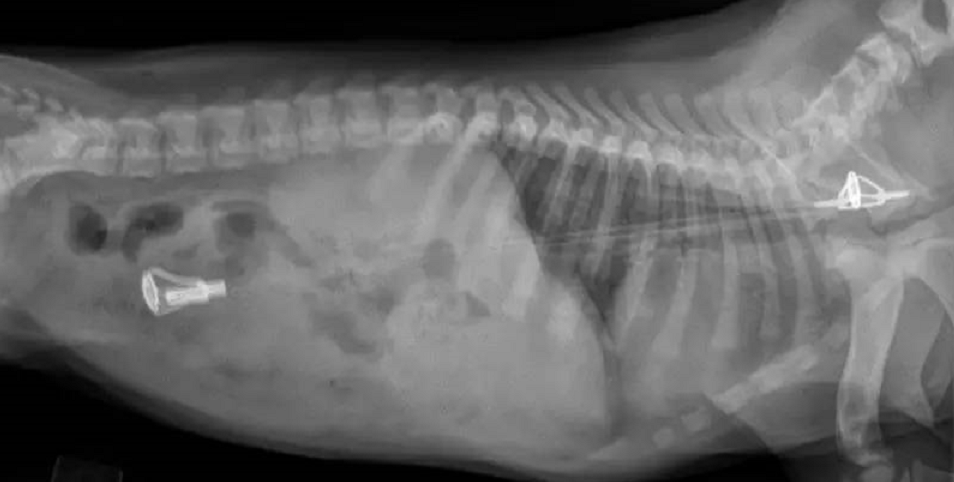

一只秋田的主人无意中发现

按压狗狗的肚子有橡皮鸭的声音!

想起狗狗很爱玩橡皮鸭,

就立马带去医院拍片,

果然拍出肚子里有一堆!

因为鸭鸭的形状比较规则,

而且狗子也比较大只,

医生可以用内窥镜帮狗狗“提货”,

逃过了开刀的痛苦。

笑死,主人还带了一只鸭鸭供医生参考

最后成功救出了6只鸭鸭